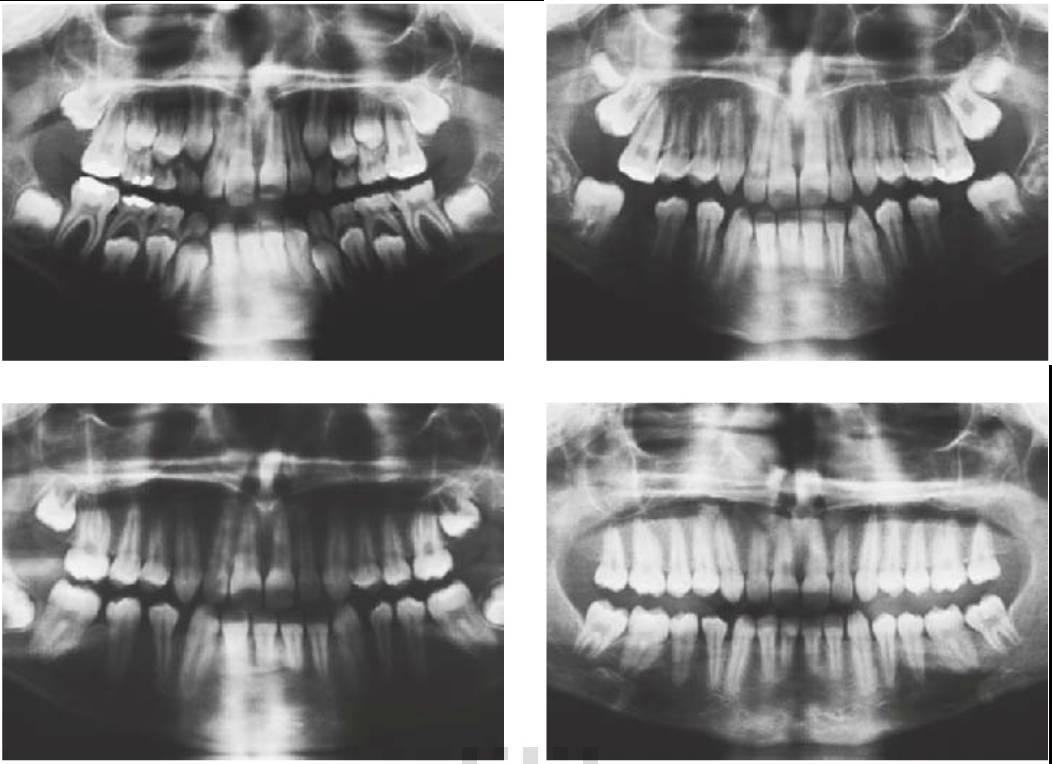

Secuencia del tratamiento (figs. 11.21, 11.22)

- Selección del caso y planificación del tratamiento.

- Preparar registros completos.

- Necesidad de retirar de forma progresiva cualquier tratamiento ortodóncico prefuncional relevante o la posibilidad de movimiento simultáneo de dientes en fase activa.

- Registro de mordida: avanzar la mandíbula a la posición de borde a borde para el registro de la mordida.

- Fase activa.

- Uso y seguimiento del aparato.

- Recorte del acrílico que permita la erupción selectiva de dientes para la corrección de la mordida abierta y la corrección molar sagital.

- Fase de apoyo.

- La placa de mordida acrílica modificada mantiene la mandíbula hacia delante.

- Acabado y detalle con aparatos fijos.